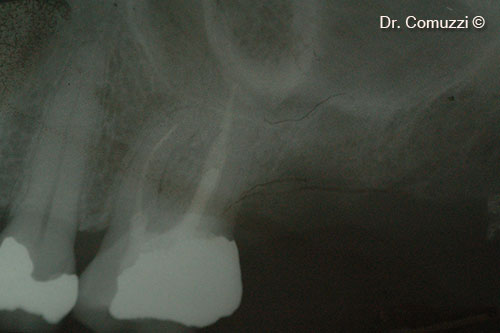

2. Initial vertical bone